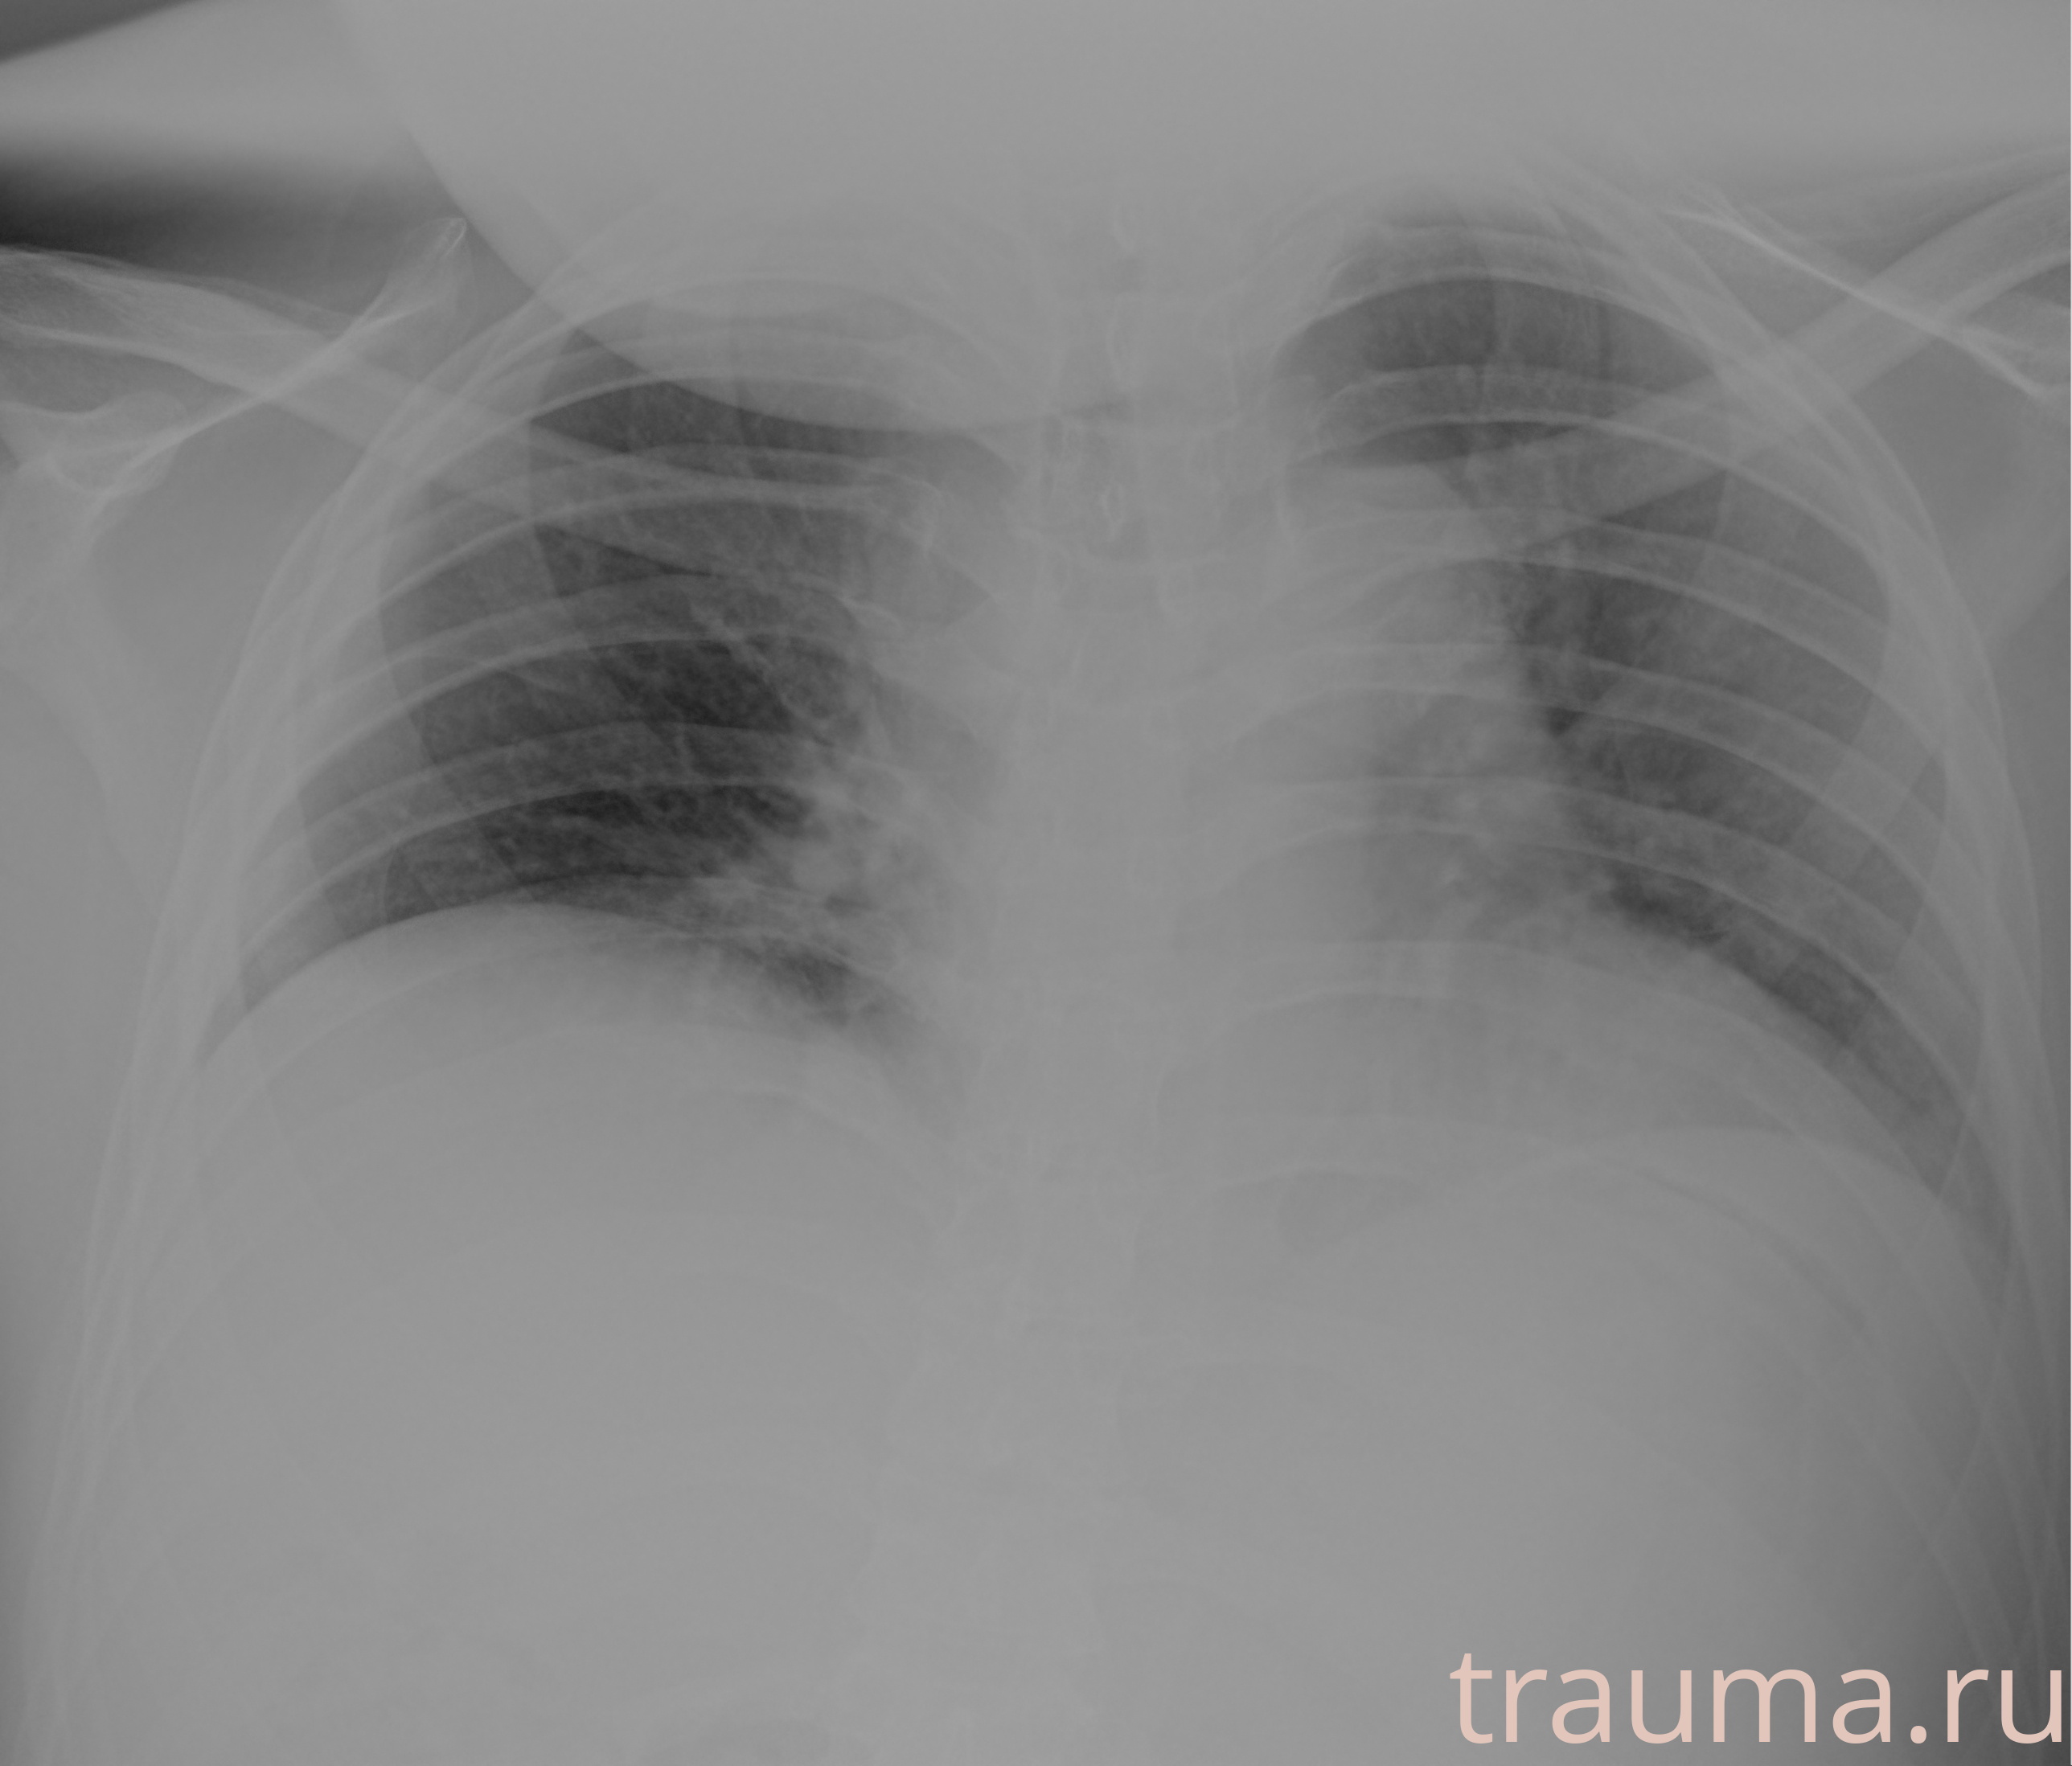

Рентгенограммы

Рентген на дому: по вашему адресу приезжает врач-рентгенолог, травматолог-ортопед с мобильным рентгеновским аппаратом, проводит диагностику травмы или заболевания, делает необходимые рентгенограммы, дает рекомендации по дальнейшему лечению. Получить качественные снимки в домашних условиях возможно благодаря уникальной методике, разработанной МосРентген Центром для института  Склифосовского

при переломе шейки бедра и пневмонии от компании МосРентген Центр - партнера Института имени Склифосовского